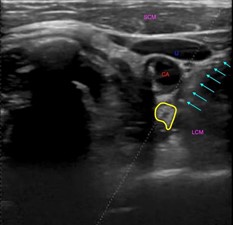

SGB is within the scope of any emergency physician proficient in the use of POCUS, however the blocks described here were performed by ultrasound fellows. Continuous visualization of the needle (Figure 2) is necessary especially during ongoing compressions in order to decrease the chance of complication. Multiple studies have shown ultrasound guidance for SGB improves efficiency and precision and allows for a smaller injection volume [8-10]. 5mL of 2% lidocaine was injected in each case presented here (Figure 3).

Figure 2: Transverse ultrasound image of the lateral neck showing a needle approaching the stellate ganglion in the long axis (teal arrows). Carotid artery (CA), internal jugular vein (IJ), longus colli muscle (LCM) and sternocleidomastoid muscle (SCM) again labeled. Stellate ganglion outlined in yellow.